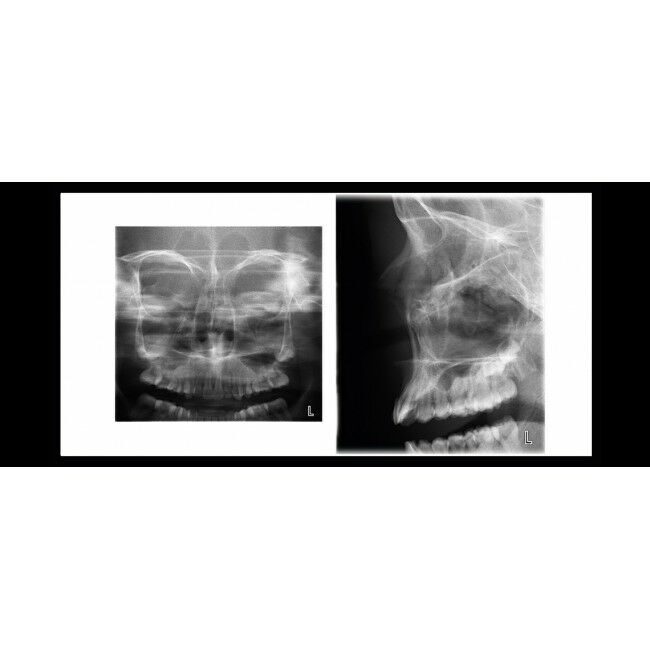

Боковая и двойная ВНЧС программа,

Задне-передняя двойная ВНЧС программа,

Полностью цифровой рентгеновской установкой Planmeca ProOne очень легко пользоваться благодаря технологии cutting edge. Широкий выбор программ облучения и параметров графического интерфейса для пользователя гарантируют, что рентгенологические исследования всех видов выполняются очень быстро и без каких-либо усилий. Будучи небольшого размера, установка Planmeca ProOne предоставляет все преимущества цифрового изображения.Установка Planmeca ProOne обладает разнообразными программами для всеобъемлющего получения изображения в разных рентгенографических целях. Помимо стандартной программы панорамного изображения в установке Planmeca ProOne предусмотрены программы для получения изображений TMJ и синуса.